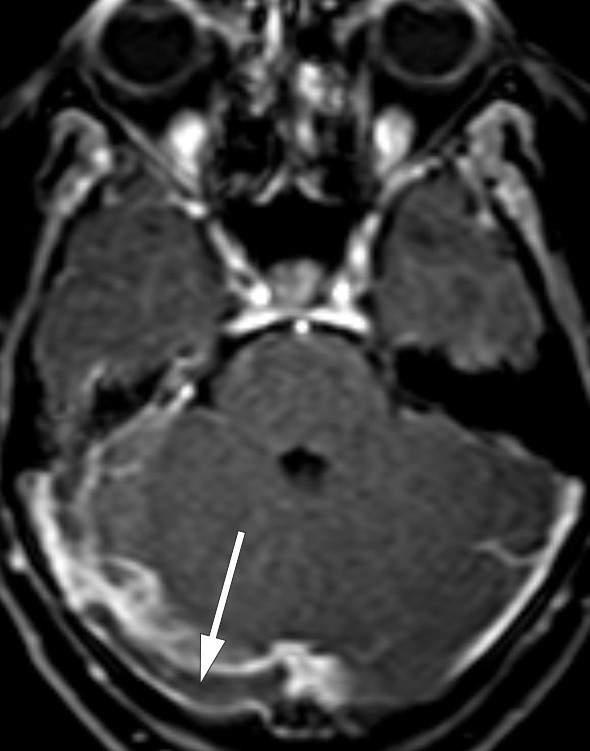

Cerebral CT-undersøkelse viste intet sikkert, men det ble stilt spørsmål om det kunne være noe patologisk i intrakraniale vener. T1-vektet MR-bilde av bakre skallegrop etter kontrastinjeksjon viste trombe i høyre sinus transversus (fig 1), mens venstre side var åpen.

Et mindre antall tilfeller som er blitt studert anatomisk og med CT- eller MR-undersøkelse, indikerer at prosopagnosi som oftest er assosiert med bilaterale lesjoner av mediale oksipitotemporale regioner. Det er rapportert unntak som skyldes unilateral skade, nesten alltid på høyre side (14). Hos vår pasient forelå det en trombe i sinus transversus på nettopp høyre side (fig 1). Venøs drenasje fra temporallappen skjer til sinus transversus via vena Labbé (vena anastomotica inferior), og stase i denne venen kan gi sirkulasjonsforstyrrelse i aktuelle hjerneområde. På MR-bildene var det ingen holdepunkter for diffusjonsavvik eller andre parenkymforandringer. Imidlertid lot ikke vena Labbé seg fremstille på aktuelle side, mens det var godt signal i kontralateral vene (fig 3). I sum anser vi at en sammenheng mellom MR-funn og pasientens kognitive symptomer er sannsynlig.